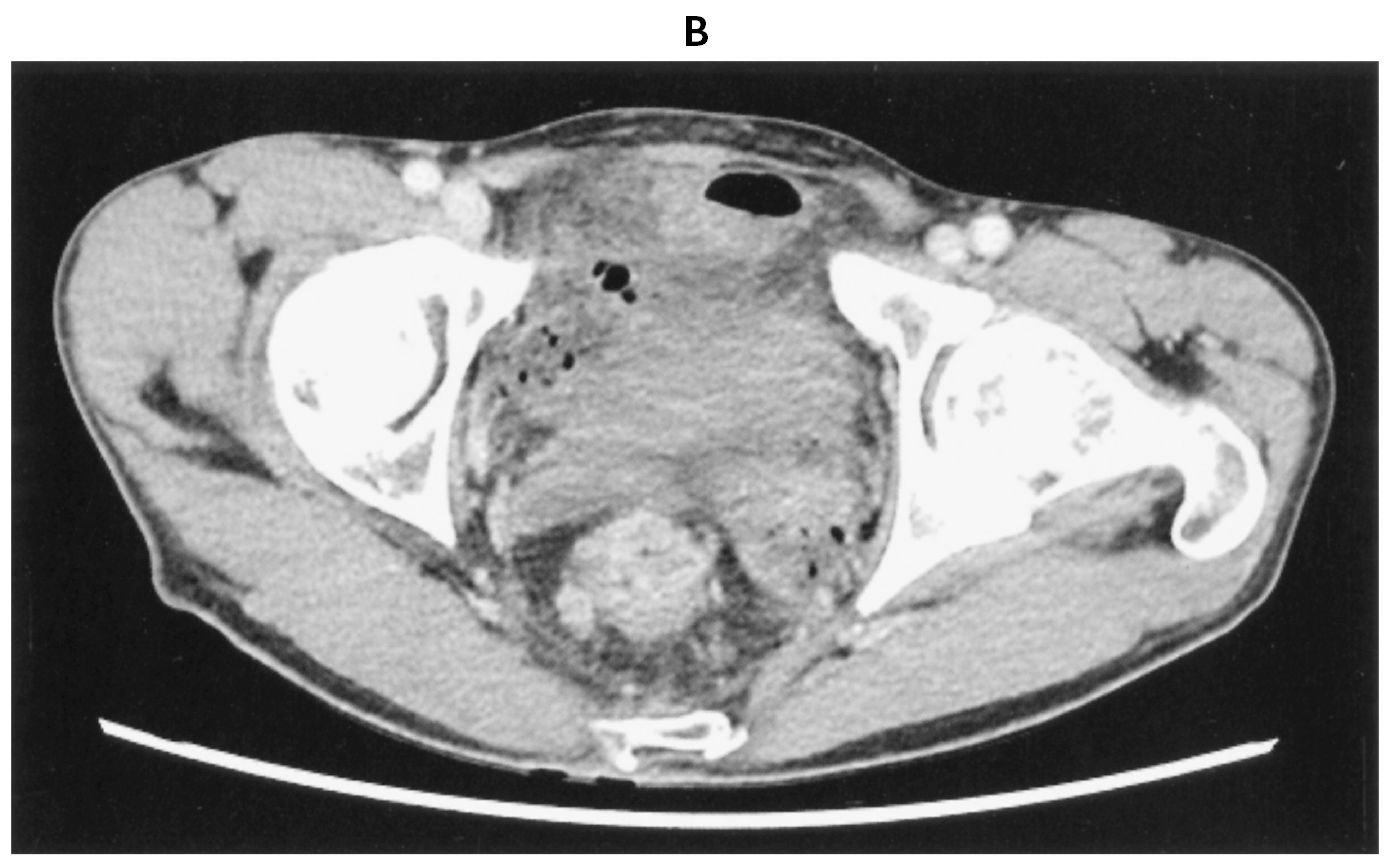

45歳の男性。下血を主訴に来院した。1か月前から排便時の出血を自覚していた。既往歴に特記すべきことはない。喫煙は20本/日を25年間。飲酒歴はない。意識は清明。身長170cm,体重54kg。体温36.4℃。脈拍68/分,整。血圧112/68mmHg。呼吸数12/分。SpO2 96%(room air)。眼瞼結膜と眼球結膜とに異常を認めない。心音と呼吸音とに異常を認めない。腹部は平坦,軟で,肝・脾を触知しない。血液所見:赤血球508万,Hb 15.2g/dL,Ht 45%,白血球6,400,血小板24万。血液生化学所見:総蛋白7.2g/dL,アルブミン4.8g/dL,総ビリルビン1.0mg/dL,直接ビリルビン0.2mg/dL,AST 18U/L,ALT 16U/L,LD 166U/L(基準124~222),ALP 63U/L(基準38~113),尿素窒素12mg/dL,クレアチニン0.8mg/dL,血糖92mg/dL,CEA 10.2ng/mL(基準5以下),CA19-9 32U/mL(基準37以下)。CRP 0.2mg/dL。下部消化管内視鏡検査の直腸像(A)と腹部造影CT(B)とを下に示す。その他画像検査で,遠隔転移は認めなかった。開腹手術を行うことにした。